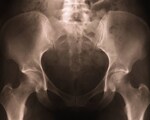

Researchers in USA had noticed evidence of pelvic widening in X-rays from patients. They searched the scientific literature and found no previous studies that directly examined whether or not the skeleton continues to widen after skeletal maturity. To examine this question, they randomly selected 246 patients in various age groups (20 male and 20 female patients in each 10-year age group, from the 20-29 age group to the 70-79 age group). The patients' CT scans were examined to measure the width and height of the L4 vertebral body (as an indication of whether these patients were taller and larger overall), the width of the pelvic inlet (the birth canal opening in the middle of the pelvis), the distance between the femoral heads (hip joints) and the diameters of the femoral heads.

The study found the width of the patients' pelvises continued to grow, even after skeletal maturity at 20 years of age. Specifically, the researchers noted, the pelvic inlet (the birth canal opening in the middle of the pelvis) widened, which is evidence of actual pelvic growth.

On average, the pelvic width of the oldest patients in the study was nearly an inch larger than the youngest patients. The study's authors explained this one-inch increase in pelvic diameter, by itself, could lead to an approximately three-inch increase in waist size from age 20 to age 79.